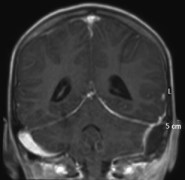

le diagnostic repose sur l’IRM mais le scanner est nécessaire pour juger de l’étendue de l’ostéite crânienne

lorsqu’il existe une ostéite frontale importante associée à un empyème volumineux, le tableau clinique est assez caractéristique, avec un oedème fronto-orbitaire massif, chémosis et tableau infectieux sévère : c’est la pseudo-tumeur de Pott (Pott’s puffy tumor).